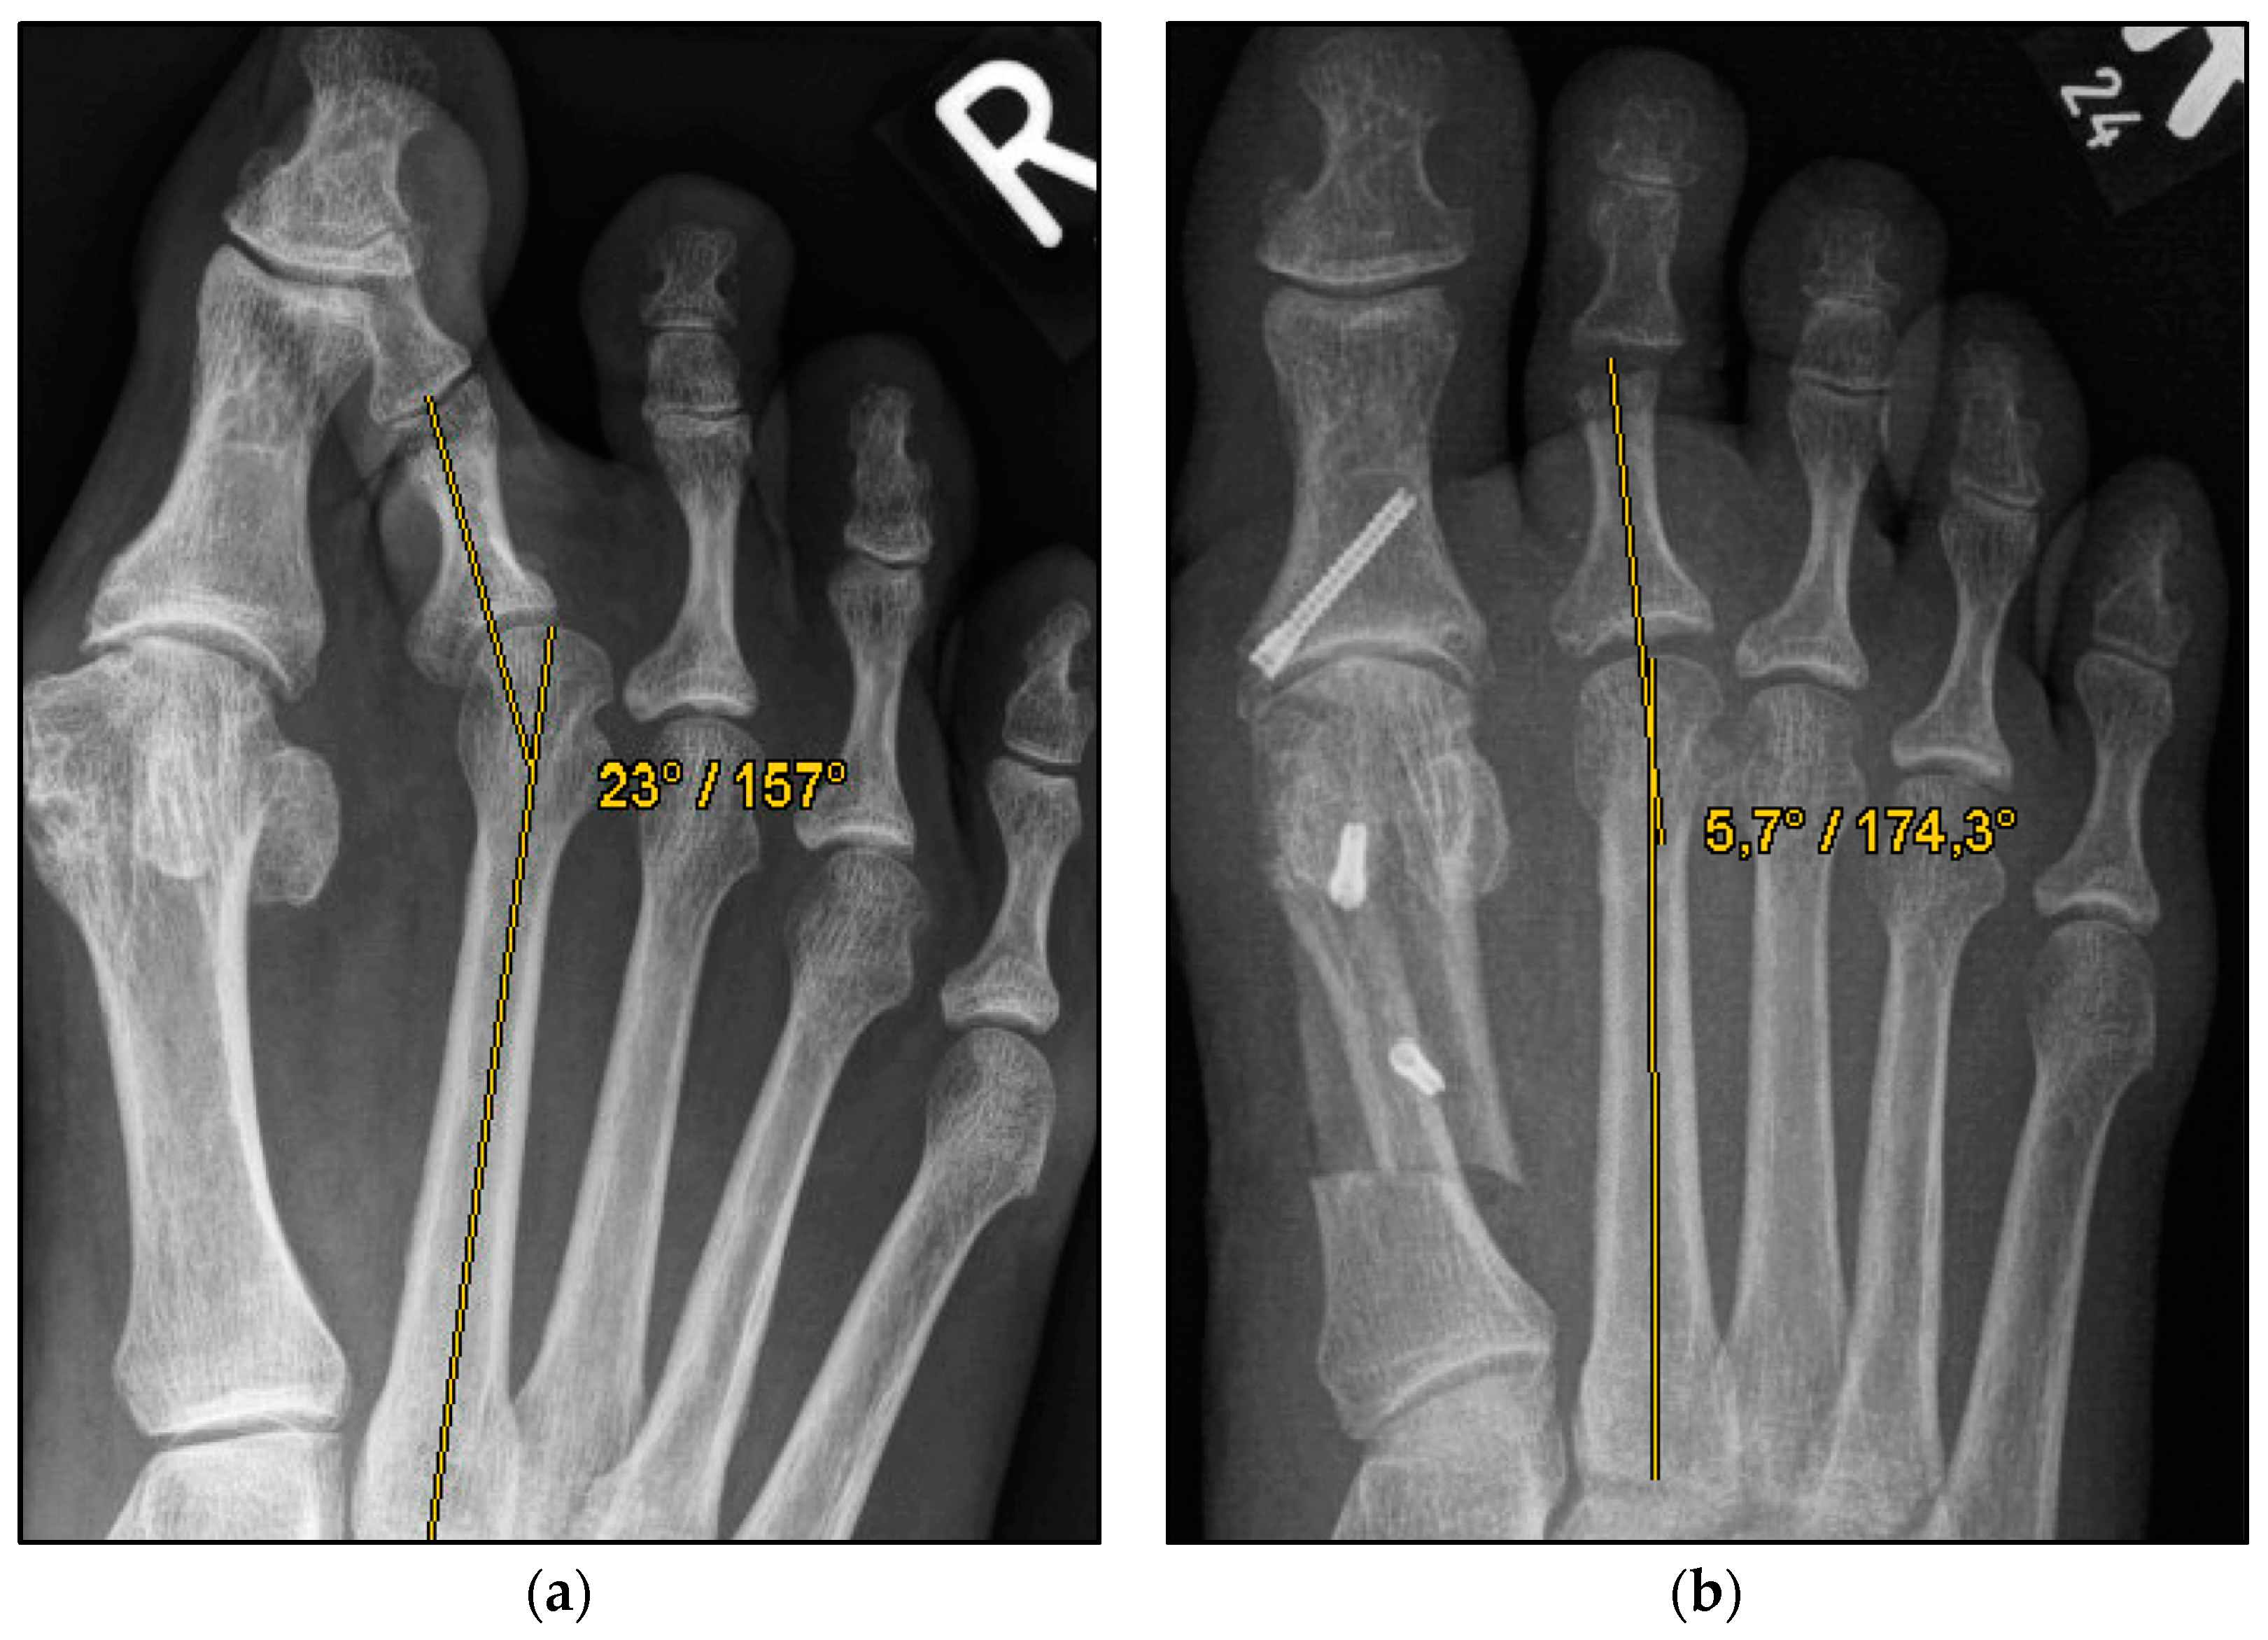

Figure 2.

Pre- and postoperative radiographic results of combined hallux valgus surgery and Weil osteotomy of metatarsal 2 (group B without screw), right foot. (a) Weight-bearing radiograph: anteroposterior view preoperative, (b) weight-bearing radiograph: anteroposterior view, 2 months postoperative.

We collected the following data from the weight-bearing dorsoplantar foot radiographs after a mean follow-up period of 16 weeks (3.6 months). With no significant difference between groups, the mean MTP angle changed from 9.24° to 12.99° preoperative to postoperative (medial deviation: −n, lateral deviation: +n). As can be seen from the mean SEM in Table 2 and Figure 4 and Figure 5, the maximum medial and lateral deviations from pre- to postoperative were significantly different. The mean MTP only changed from 9.3 to 12.9 and was in the range of a mild lateral deviation. This was also observed equally in both groups (p > 0.05). Of note, the postoperative visibility of the joint space was documented significantly more often in the group without screw fixation; this means the space between the subchondral bone of the metatarsal and the toe was seen without overlay (p < 0.05).

The underlying assumption of our study and the knowledge gained from our results can be further elaborated upon. An inharmonious transverse plane alignment can also be corrected with Weil osteotomy and does not require osteosynthetic fixation of the displaced metatarsal head [24]. The results confirm, based on postoperative weight-bearing radiographs, that the surgically induced correction is maintained regardless of screw fixation. An objectifiable criterion was the metatarsophalangeal angle measured pre- and postoperatively using weight-bearing radiographs in the dorsoplantar view (Figure 1 and Figure 2). In both treatment groups, it was possible to bring the maximum axis deviation closer to the mean value; the mean difference between pre- and postoperative metatarsophalangeal angle was only 3.8°. On average, 10.6 degrees were required to achieve the desired surgical result, regardless of screw fixation (Figure 4 and Figure 5). However, the significantly higher possibility of viewing the affected metatarsal joint space postoperatively can also be considered a successful outcome of the restoration without screw fixation. The visibility of the articular surface, in turn, proves the centering of the metatarsal head in the transverse plane as well as a sufficient correction in the sagittal plane (Figure 6 and Figure 7) [25]. Again, the inability to view the joint space indicates that inadequate correction of the claw toe deformity as well as the metatarsal, which was considered “too long”, was performed [1,14,26].